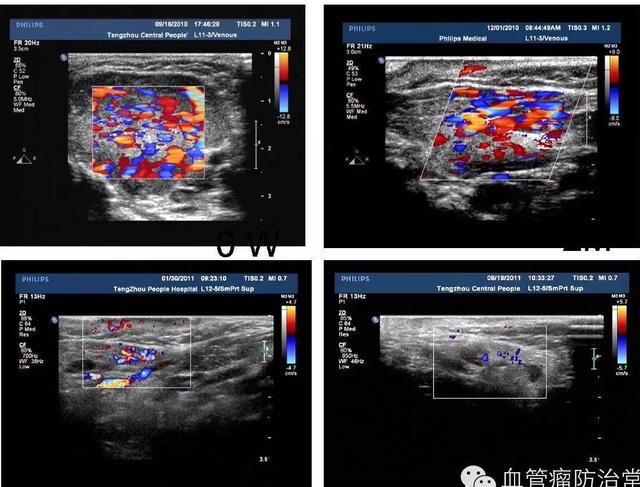

(4月女嬰,腮腺部巨大血管瘤,因生長快形成潰瘍??诜牡冒仓委?周內(nèi)潰瘍愈合。隨訪患兒到4歲,無復(fù)發(fā),血管瘤體及彩超血流信號全部消退)

對就診時瘤體較大或者口服心得安不能控制的血管瘤患兒,采用新型硬化劑聚桂醇瘤體內(nèi)注射治療,便可治愈大多數(shù)血管瘤患兒。該方法無創(chuàng)傷,無明顯并發(fā)癥。我院在國內(nèi)較早開展超聲引導(dǎo)下硬化劑注射治療血管瘤,明顯縮短了治愈時間,減少了治療費(fèi)用。